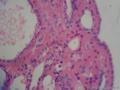

乳头状癌?

女    58岁      破碎紫红组织一堆V:3X2.5X1CM。

补取,好多毛玻璃样核。

结甲伴乳头状增生

结甲囊性变伴滤泡上皮乳头状增生